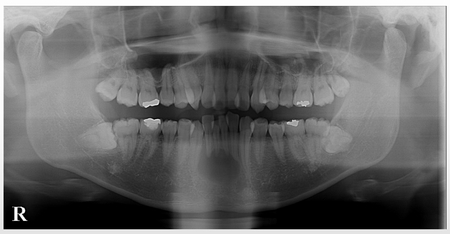

レントゲン写真をみると大きな黒い影があります

かなり大きな根尖病変のようです